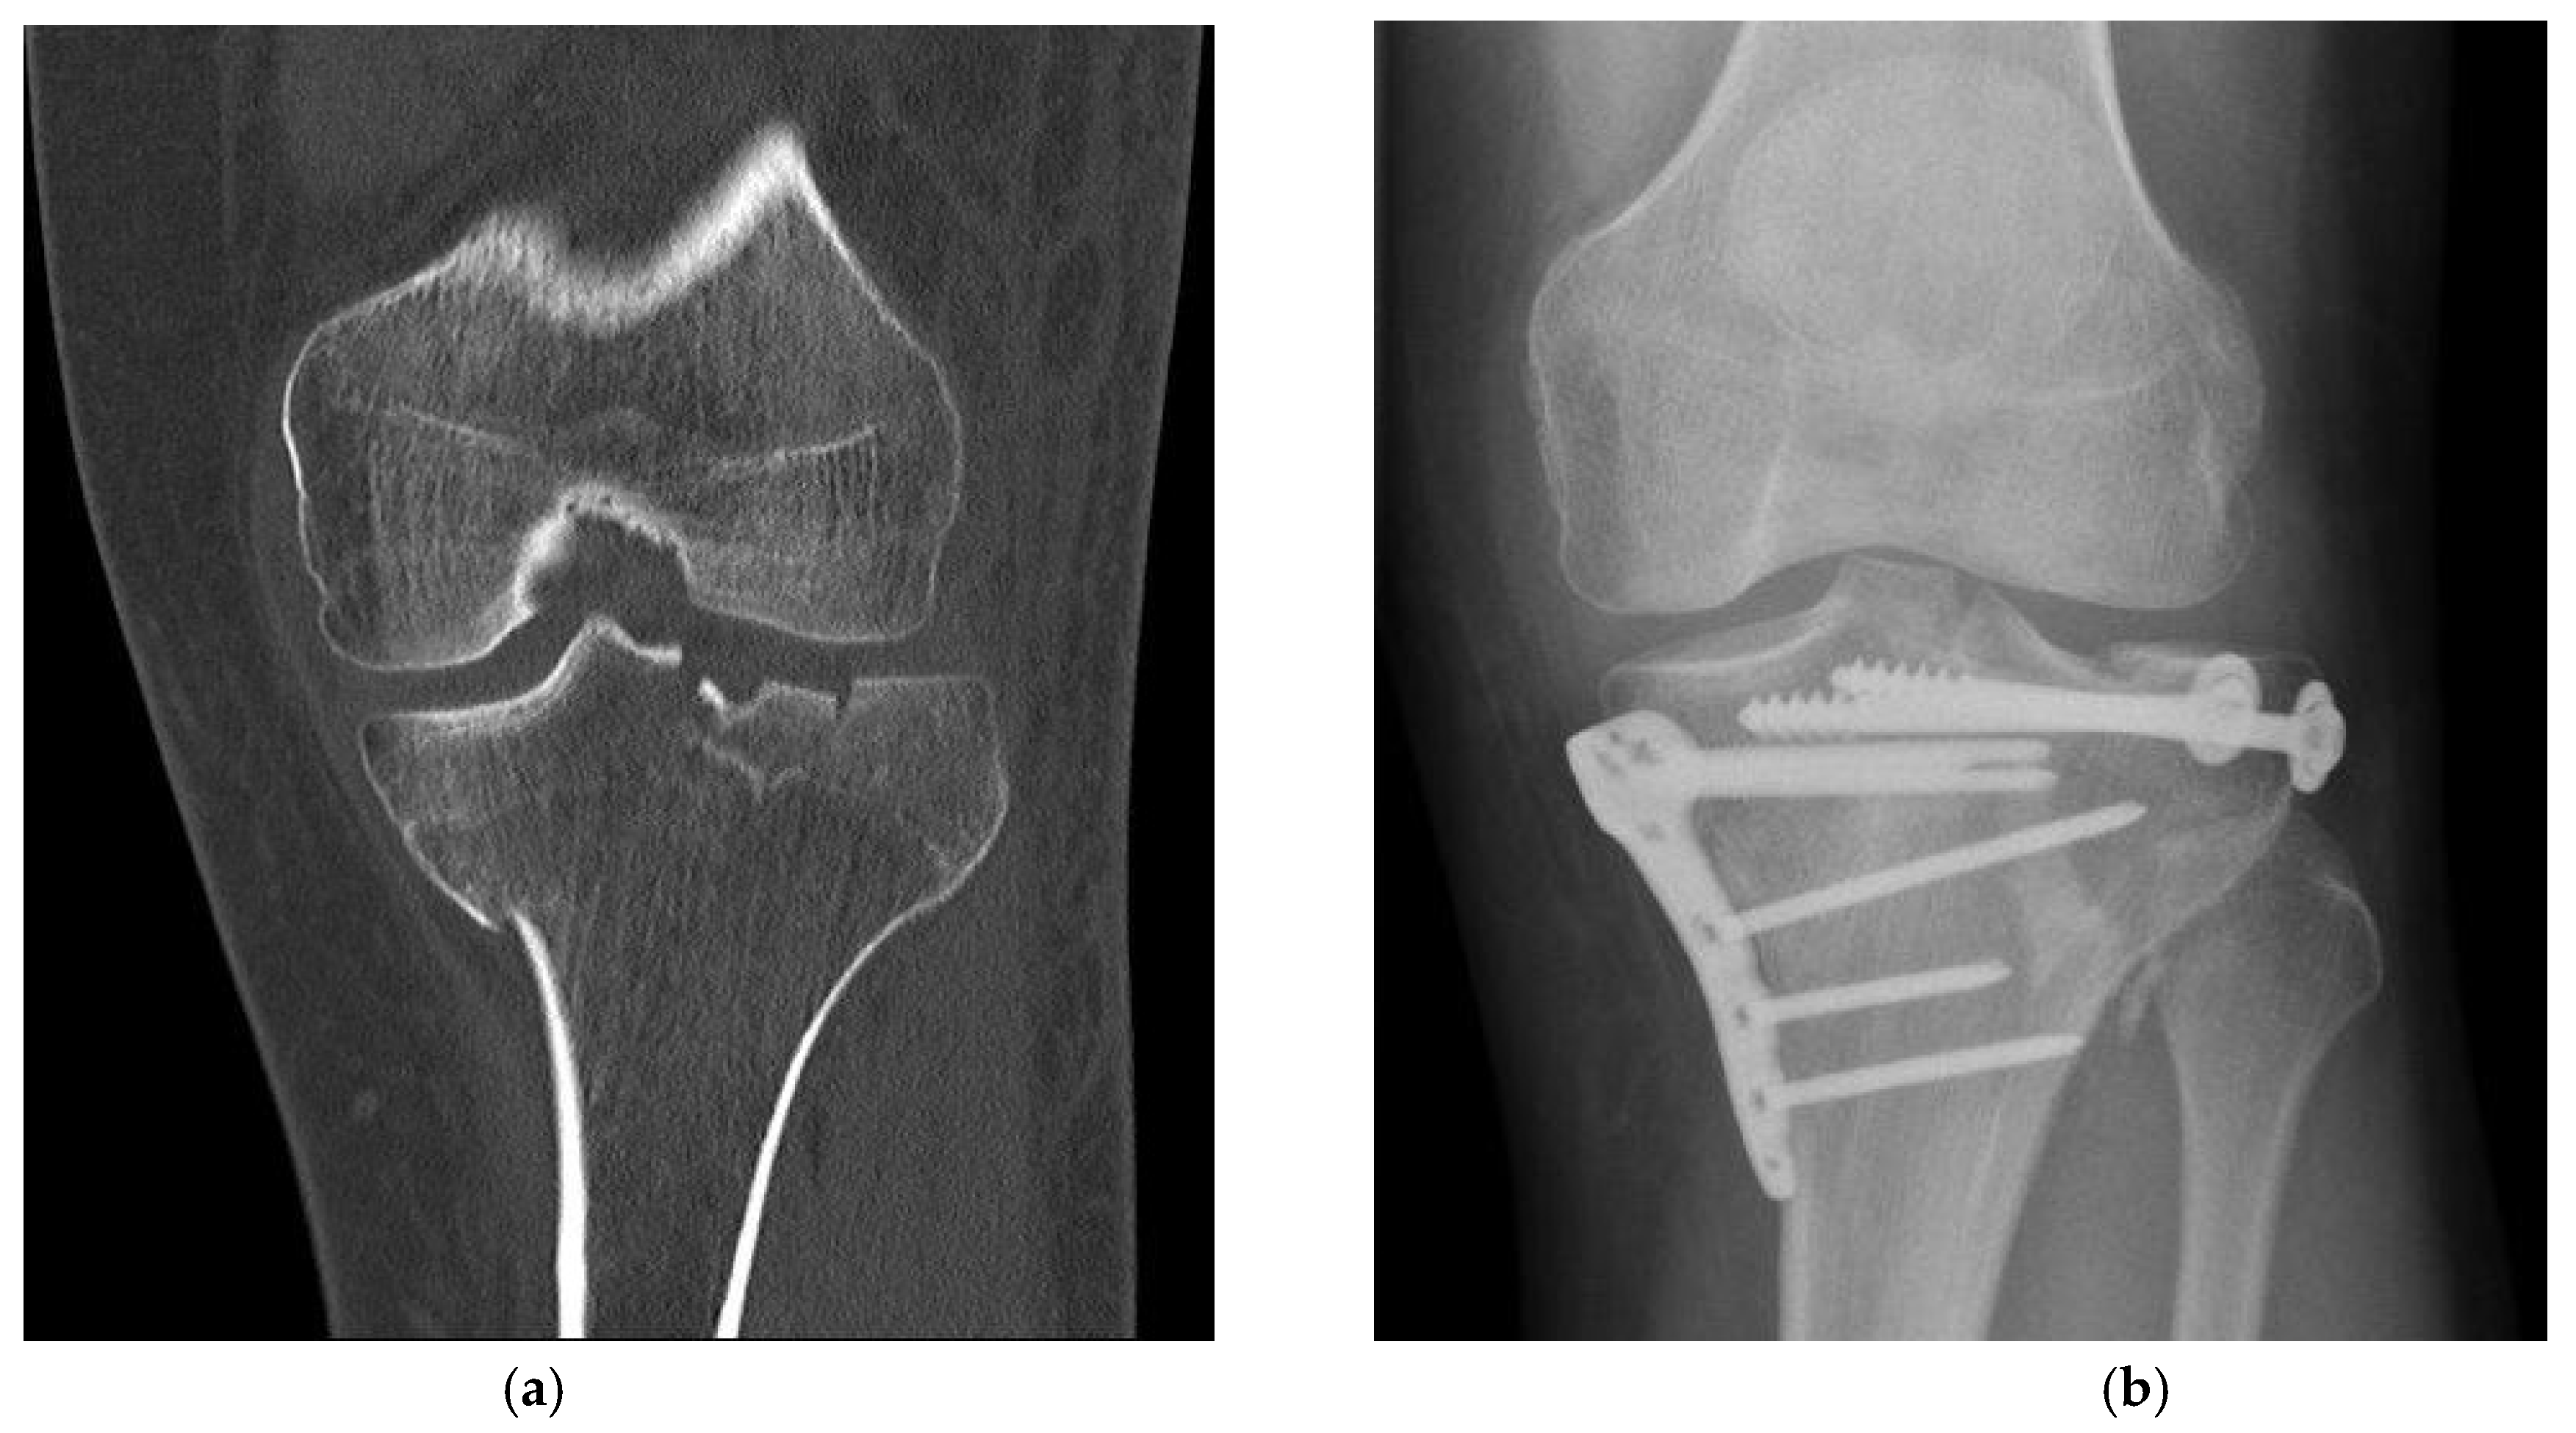

Figure 2. Fracture treatment of a proximal tibial fracture by surgical bone substitute material augmentation: (a) Preoperative CT scan demonstrates an metaphyseal compression fracture with intra- and extraarticular fracture gaps; (b) Alloplastic bone material substitute augmentation replaces the bone material of the fracture vault defects.